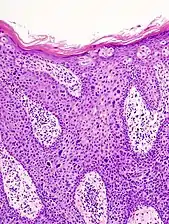

In situ disease

Bowen's disease is essentially equivalent to and used interchangeably with cSCC in situ, when not having invaded through the basement membrane.[12] Depending on source, it is classified as precancerous[13] or cSCC in situ (technically cancerous but non-invasive).[45][46] In cSCC in situ (Bowen's disease), atypical squamous cells proliferate through the whole thickness of the epidermis.[12] The entire tumor is confined to the epidermis and does not invade into the dermis.[12] The cells are often highly atypical under the microscope, and may in fact look more unusual than the cells of some invasive squamous-cell carcinomas.[12]

cSCC in situ, high magnification, demonstrating an intact basement membrane.[12]